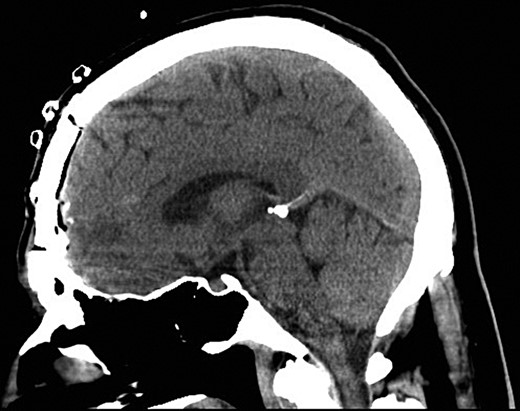

The patient had three postoperative seizures within 24 h of the surgery. He was commenced on phenytoin in addition to levetiracetam. The postoperative period was otherwise unremarkable. A postoperative CT was performed which demonstrated removal of all needles (Fig. 3). He was discharged home Day 3 with no further seizures. The patient remained seizure free at 6-month follow-up.

Sagittal postoperative CT scan demonstrating successful removal of the needles.